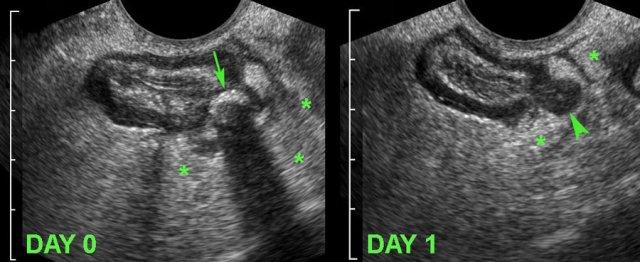

Bệnh nhân nữ, 34 tuổi, nhập viện vì đau cấp tính hố chậu trái.

TVUS ghi nhận thành đại tràng sigma dày khu trú và một túi thừa chứa sỏi phân (mũi tên), được bao quanh bởi lớp mỡ viêm (*), đại diện cho mạc treo và mạc nối, có tác dụng bao bọc ngăn chặn tình trạng thủng sắp xảy ra.

Ngày hôm sau, bệnh nhân cảm thấy tốt hơn nhiều và TVUS theo dõi cho thấy túi thừa rỗng, giảm âm, thành dày do phù nề (đầu mũi tên).

Sỏi phân dường như đã được tống xuất vào lòng đại tràng sigma.